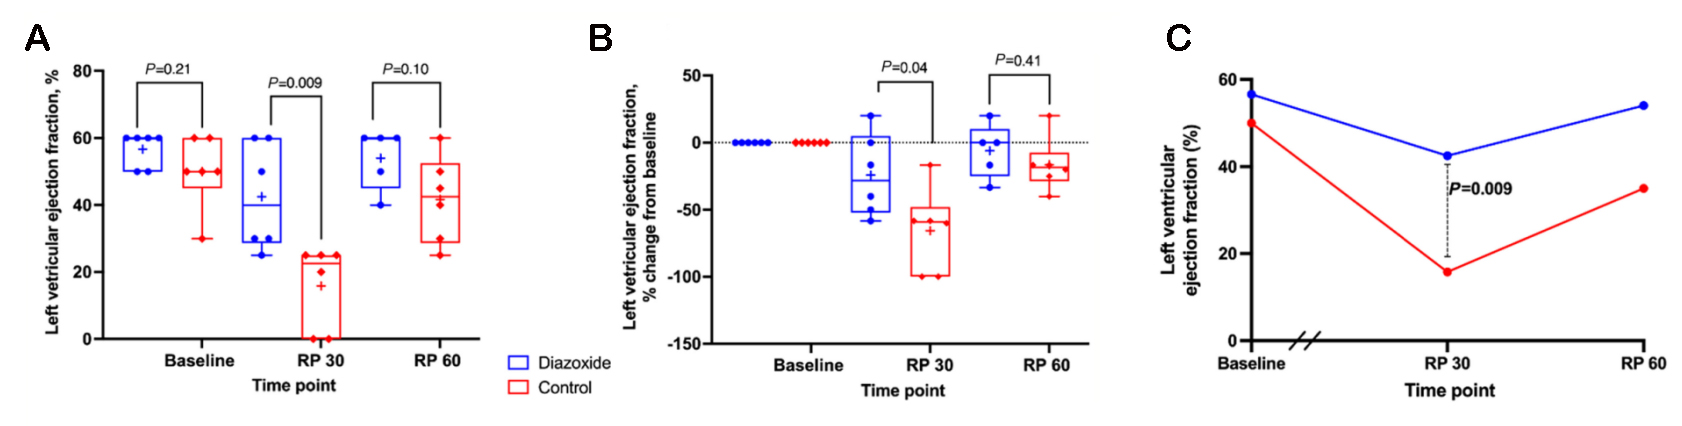

An early study in 2005 comparing diazoxide to control in a porcine model found that diazoxide did not provide cardioprotection (infarct size and systolic function) after myocardial ischemia[133]. The authors acknowledged that their results were incongruent with others’ findings and postulated that this could be due to preconditioning effects of anesthetics or an incorrect dose of diazoxide. Recent studies have been more promising. In an isolated mouse heart model, adding diazoxide to cardioplegia led to improved diastolic function following a period of global ischemia[134].Two subsequent studies were conducted in swine models. In the first, swine treated with hypothermic, hyperkalemic cardioplegia with diazoxide (single dose) prior to a 2-h global ischemic period were found to have improved systolic and diastolic ventricular function compared to cardioplegia alone [Figure 2][135]. In the second, swine underwent 30 min of occlusion of the left anterior descending artery prior to 2 h of global ischemia protected with cardioplegia or cardioplegia with diazoxide (dosed every 20 min) [Figure 3][136]. Compared to cardioplegia alone, animals that received diazoxide had decreased myocardial stunning and shortened time to separate from cardiopulmonary bypass [Figure 4][136]. These studies provided some of the most convincing preclinical data to date that diazoxide will be beneficial as an additive to cardioplegia in humans undergoing cardiac surgery requiring global ischemia. It is important to acknowledge the limitations of the translational models that have been widely used to study KATP channels and cardioprotection. These models may not provide sufficient confidence to translate to human pathophysiology. These limitations highlight the importance of randomized clinical trials in humans before widespread adoption.

Figure 4. KATP channel opener diazoxide was associated with improved left ventricular ejection fraction at 30 min after reperfusion in a porcine model of 30 min of regional ischemia followed by 2 h of global ischemia, simulating clinical cardiopulmonary bypass in the acutely injured heart prior to cardiac surgery. Using a translational porcine model of regional ischemia (30 min) followed by 2 h of global ischemia, animals were randomized to one of two groups: cardioplegia alone (red, n = 6) or cardioplegia plus diazoxide (blue,